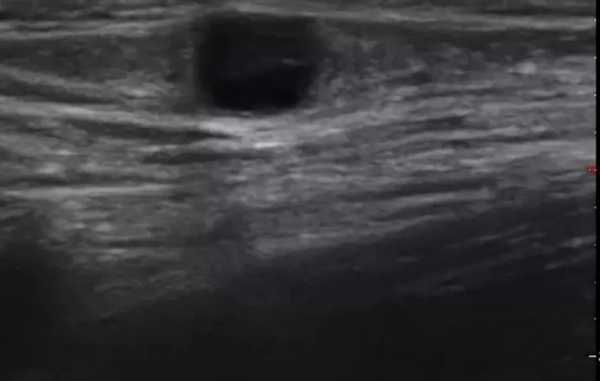

Аденопатия инфекционного генеза на сонограммах характеризуется следующими изменениями в строении ЛУ:

- нечеткостью границ;

- увеличением в диаметре - в среднем до 2-4 см;

- неоднородностью структуры;

- нарушением целостности капсулы - показатель прорыва воспалительной жидкости в соседние ткани.

Осложнения при заболеваниях ЛОР-органов влияют на особенности УЗ-визуализации лимфоузлов шеи - последние на экране ультразвукового сканера могут выглядеть как анэхогенные жидкостные образования либо как участки низкой и высокой эхогенности, чередующиеся друг с другом. Указанные изменения на снимках характерны для гнойного расплавления и формирования аденофлегмоны.